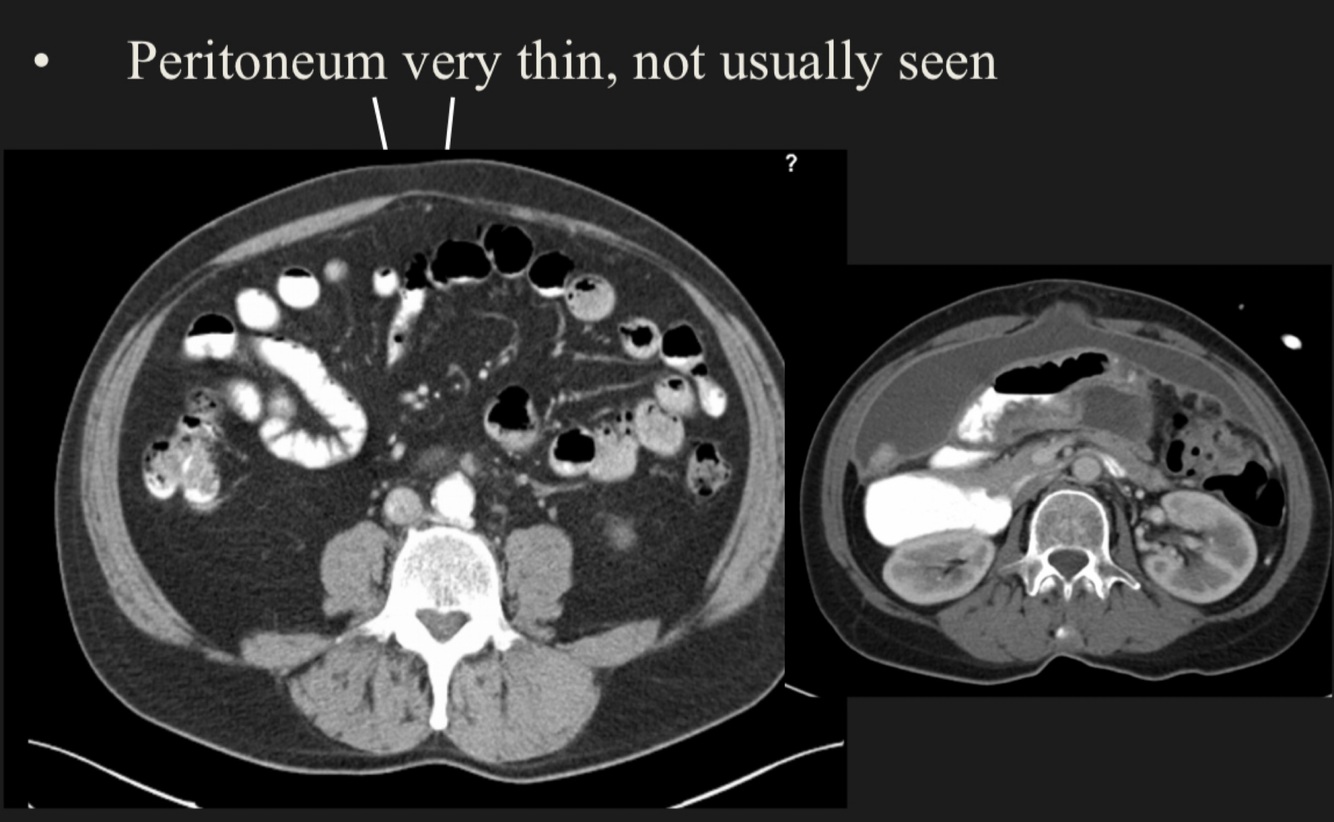

Can the peritoneum be seen in radiological techniques?

A

It is very difficult to be seen, just when there is pathology it can be seen.